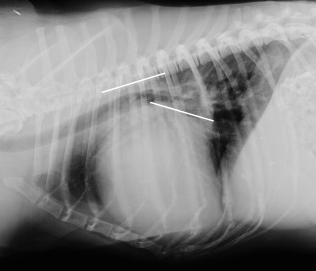

이외에도 심장의 크기를 숫자로 평가하려고 하는 수많은 노력들이 있는데

이런것도 있고

이런것도 있다.

여러가지 선들을 그어가면서 새로운 지표들이 부지불식간에 쏟아져 나오고 있다는 것은 알고 있어야 한다.